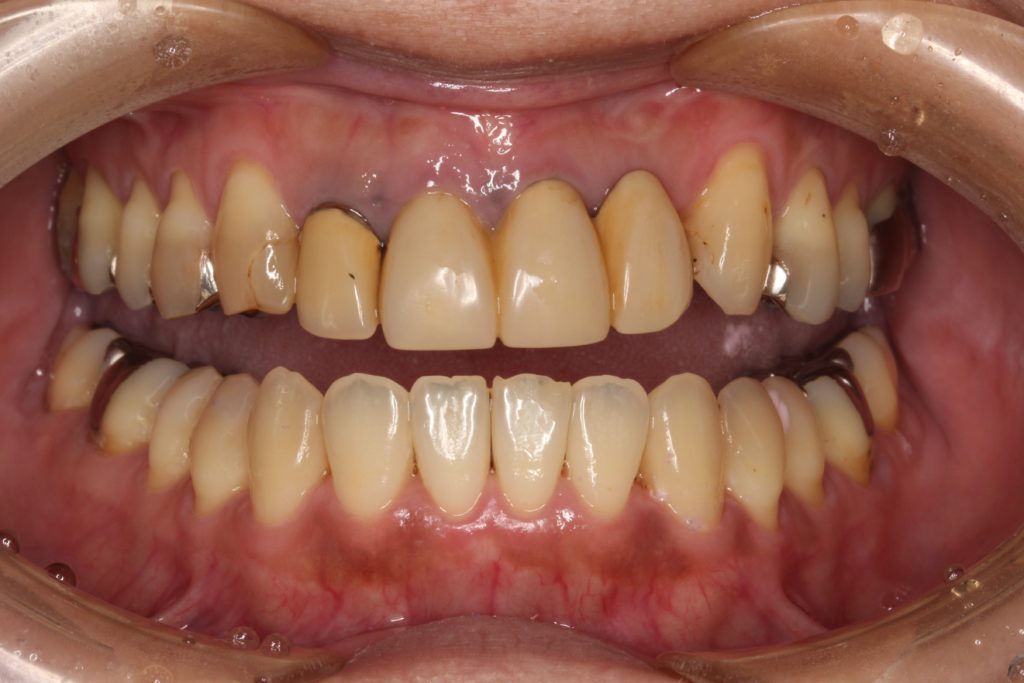

今回は前歯の審美治療の紹介です。

40代女性の患者さんです。

「昔に保険で治したブリッジの差し歯を綺麗にしたい」

と当院を来院されました。

お口の中を見てみると、

このような状態です。

前歯の4本がぶせ物で治療がされています。

こちらの4本ですね。

20年以上まえの治療で、歯が黄色く黄ばんで、歯の根元が黒くなっている箇所もあります。

こちらは「レジン前装冠」というかぶせ物で、表面の見える所はレジンというプラスティック樹脂で、内部から裏側には金属が使われています。

レジンは経年劣化とともに、黄色く変色してくる欠点があります。

そのために、歯が黄色く変色して、他の歯と色の違いが出てきます。

また内部に金属が使われていると説明しましたが、金属が歯の根元で黒く見える場合があります。